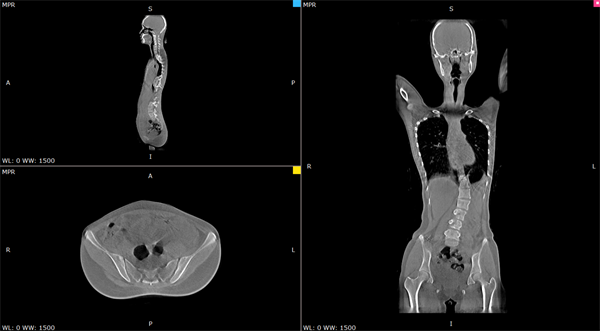

其一:【全】是采用完全三维扫描方式实现的。其基本原理是采用CBCT技术来进行成像,通过球管发射锥形束到动态平板探测器上,旋转站台带动患者匀速旋转一圈,来获得患者扫描部位负重位三维影像信息,能够真实反映患者扫描部位影像,并且可在此断层影像基础上进行MPR多平面重组、VR体绘制、MIP最大密度投影等三维重建。同时负重三维影像能够突破二维及卧位三维影像局限,真实反应人体骨与关节在三维空间,以及自然承重下的状态,扫描结果精准,有利于患者的术前规划及术后评估。

其二:【全】具备全身骨与关节应用。能支持负重位状态下的全脊柱、全下肢,以及单部位(含颈椎、腰椎、髋关节、膝关节、踝关节、气道等)的三维扫描成像,准确反映人体承重情况下的关节状态。对于脊柱侧弯这种三维畸形来说,负重位二维平片只能够提供冠状面影像信息,不同的椎体空间扭转情况在二维平片上可能会呈现相同的投影,影响诊疗;卧位三维成像方式,无法呈现患者真实状态下脊柱形态,同样无法为患者提供精准诊疗;而负重位锥束CT就可以弥补现有影像设备的不足,为患者提供负重位状态下的全脊柱影像,辅助脊柱侧弯精准诊疗。同样对于下肢膝骨关节炎来说,负重位三维成像可以提供负重矢状面三维影像信息,辅助膝骨关节炎患者精准诊疗。

其三:【全】具备全自动AI测量系统,为脊柱侧弯评估、膝骨关节炎评估提供直观且精准的全自动测量数据,对于脊柱矫形手术、膝关节炎矫形手术的规划和复查有着重要的临床价值。【全】获得负重位三维影像图后,可以对扫描部位特征点进行选取,并进行关键参数的自动测量,例如自动测量脊柱侧弯最关键的参数COBB角,自动测量膝关节炎最关键的下肢力线等,并能够在15分钟内将测量好的三维数据自动生成测量报告。不仅大幅节省骨科医生人工测量时间,同时提升数据准确性,对于青少年脊柱侧弯筛查等大流量体检时,具备独一无二的优势。